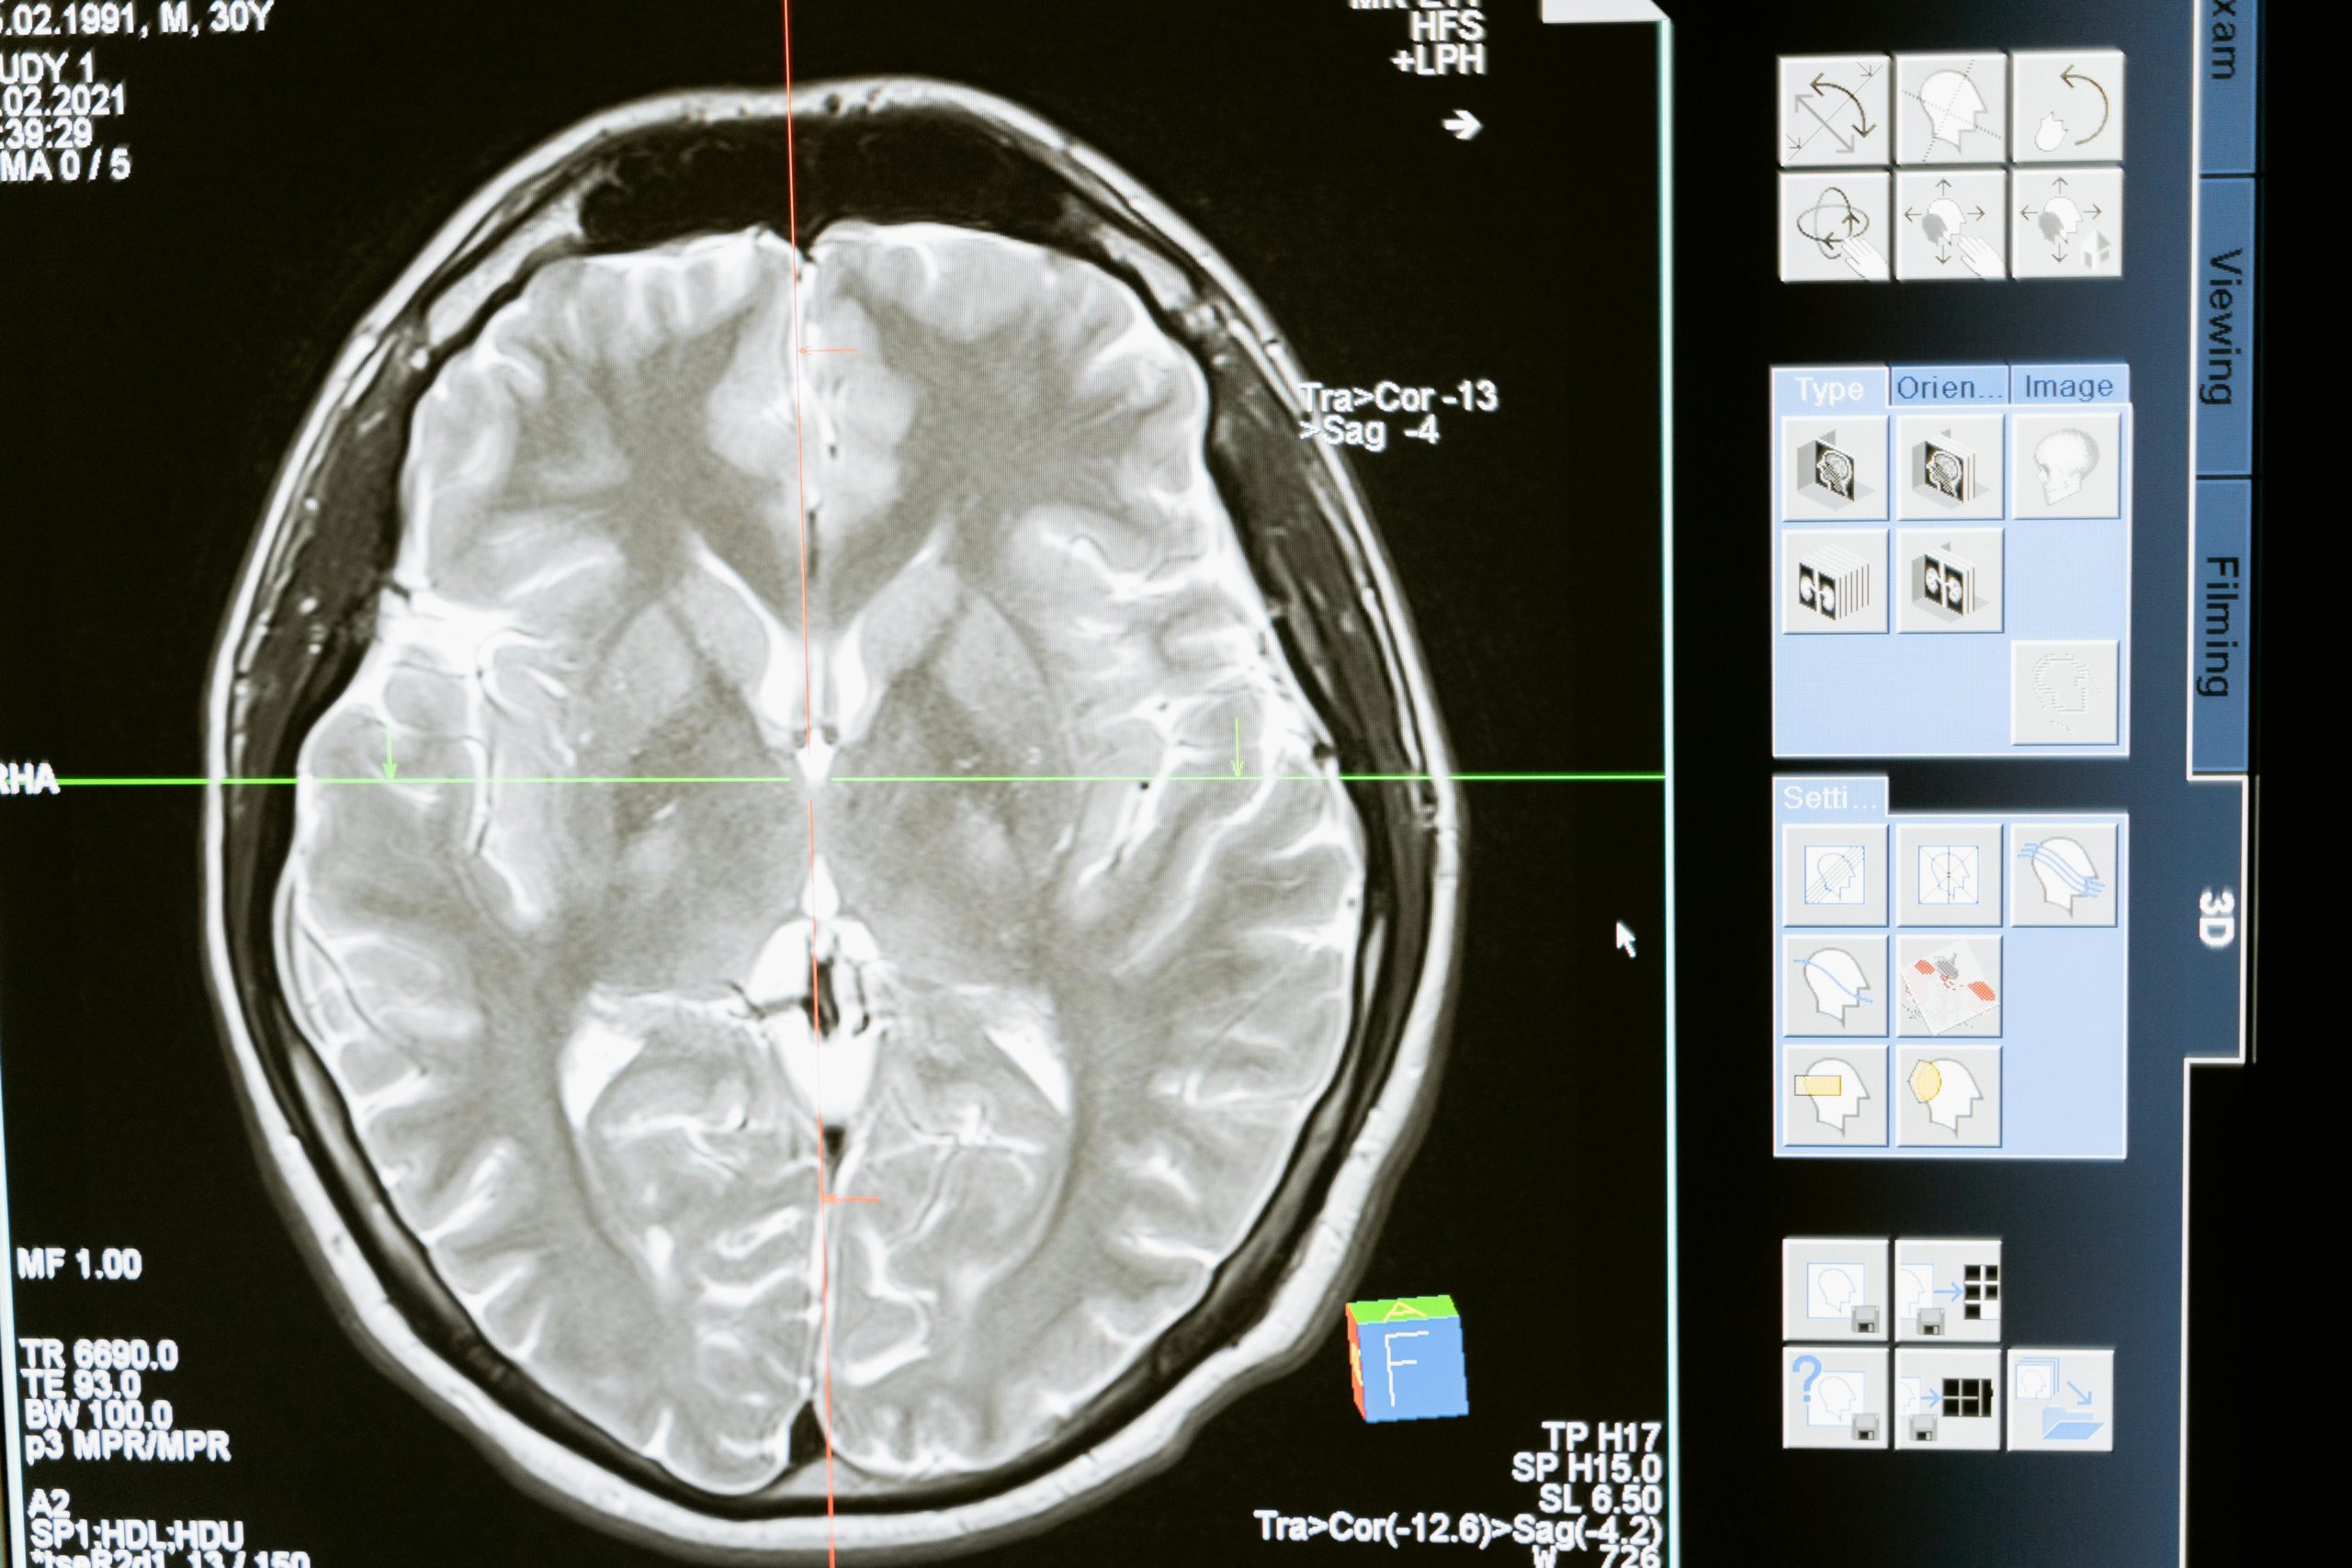

Gehirnforscher nutzen verschiedene Methoden, um im lebenden Menschen Einsicht in die Hirnaktivität zu gewinnen. Die wichtigsten Verfahren sind bildgebende Neuroimaging-Methoden und das EEG.

• MRT (Magnetresonanztomografie): Mit dem MRT können Forscher die Struktur und teilweise auch die Aktivität des Gehirns messen. Normale MRT-Bilder zeigen z. B. das Volumen von Hirnarealen oder bestimmen, ob die Anatomie normal ist. In der Lernforschung verwendet man vor allem das fMRT (funktionelle MRT). Dabei bleibt die Person in einer Röhre liegen und löst Aufgaben, während das Gerät Blutfluss und Sauerstoffverbrauch misst. Aktive Hirnregionen „leuchten“ dadurch in den Bildern auf.

• EEG (Elektroenzephalographie): Das EEG misst elektrische Hirnströme über aufgeklebte Elektroden auf der Kopfhaut. Es hat eine sehr hohe zeitliche Auflösung, so dass man nahezu in Echtzeit verfolgen kann, wie Neuronen auf Reize reagieren. Allerdings ist die räumliche Auflösung schlechter – man sieht zwar Wellenmuster, kann aber nur grob sagen, aus welchem Hirnareal sie stammen. In Lern Experimenten ist das EEG deshalb vor allem nützlich, um z. B. Aufmerksamkeitsschwankungen, Gehirn-Rhythmen oder Gedächtnisprozesse mit hoher Genauigkeit zu erfassen.